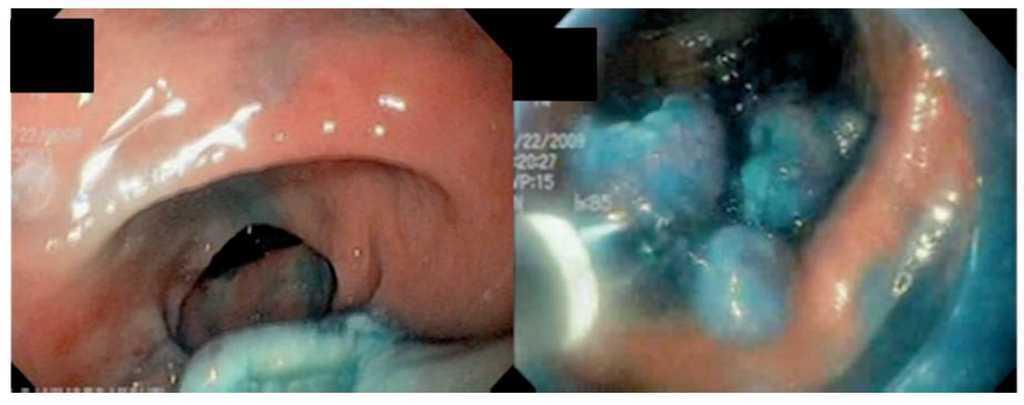

Hombre de 74 años, a quien se realizó colonoscopia por la presencia de sangre oculta en heces. Durante el procedimiento se observó una lesión en colon sigmoides, a 30 cm del margen anal, seudopediculada de base ancha y de aproximadamente 4 cm (Figura 1). Las biopsias informaron adenoma túbulovelloso con displasia de alto grado. Se le propuso cirugía para resección de dicha lesión pero el paciente rehusó este procedimiento y decidió buscar otras alternativas terapéuticas. Después de explicarle los riesgos-beneficios de la disección endoscópica aceptó el procedimiento. Se le solicitaron exámenes de laboratorio, estudios de extensión y valoración preoperatoria con resultados normales-negativos. Se le realizó disección endoscópica de la submucosa con la navaja flexible (Flex-knife), en 60 minutos y sin complicaciones (Figura 2). La pieza obtenida midió cuatro por tres centímetros (Figura 3). Después de 24 horas de hospitalización posprocedimiento, fue dado de alta sin complicaciones.

¿ Figura 2. Disección endoscópica de la submucosa con la navaja flexible.

¿ Figura 3. Resección del adenoma túbulovelloso.